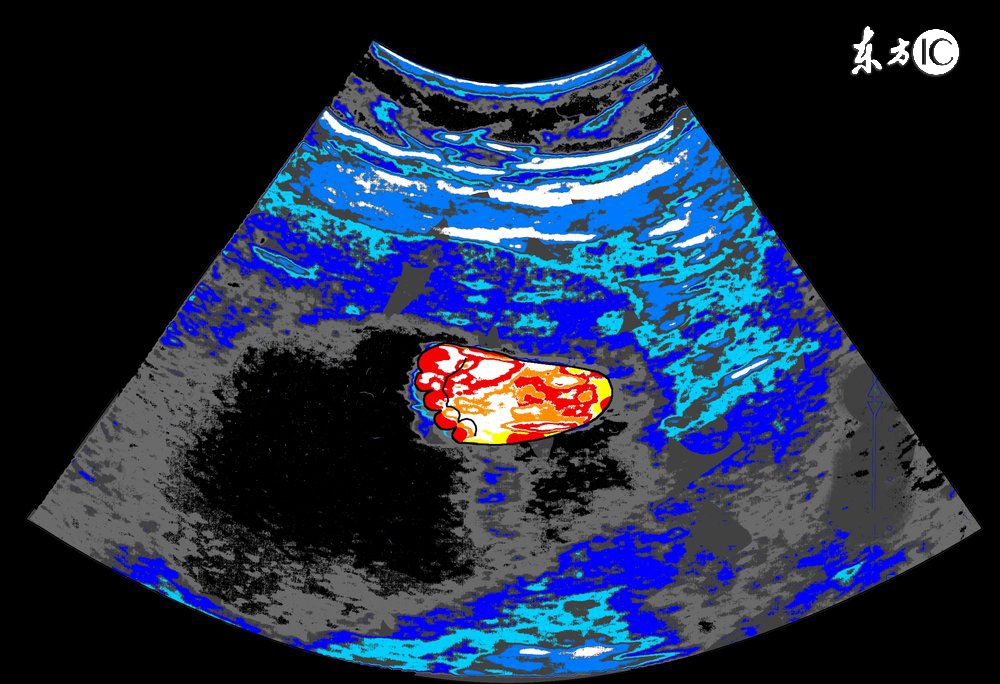

请点击此处输入图片描述

3、胎盘位置:

正常胎盘附着于子宫的前壁、后壁、宫底或侧壁,如果B超显示胎盘在子宫下段,甚至胎盘下缘达到或覆盖宫颈内口处,即为前置胎盘,前置胎盘属于高危妊娠的一种,并随着怀孕月份的增大,容易发生无痛性阴道出血,引起流产或早产。